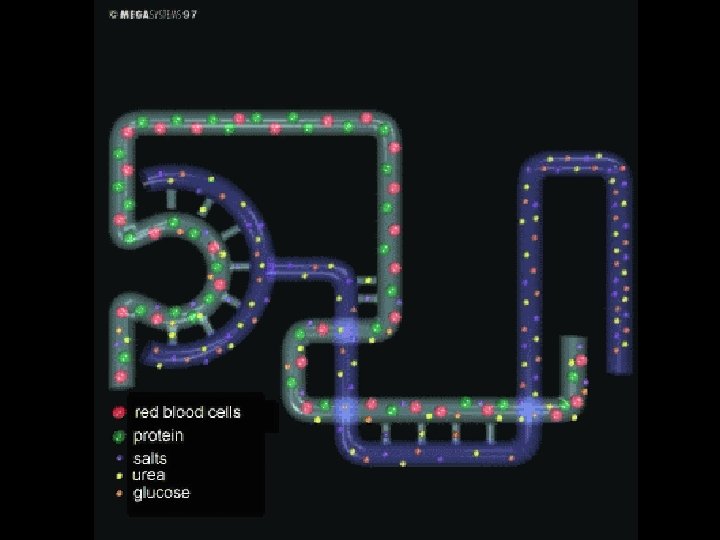

FILTRATION • During filtration, substances pass from the blood into the Bowman’s capsule. • Under pressure, water and many small molecules such as salts, urea, glucose and aminoacids pass from glomerulus into Bowman’s capsule.

REABSORBTION • The absorbtion of needed materials such as glucose, amino acids and water from nephrons to blood capillaries is called reabsorbtion. • Water is reabsorbed passively by osmosis. But reabsorbtion of glucose, aminoacids and salt ions occurs by active transport.

• All glucose, aminoacids and many salt ions are reabsorb during reabsorption. • Most reabsorbtion takes places in loop of henle. • Antidiuretic hormone (ADH or Vasopressin) regulates concentration of water in blood. • It increases water permeablity of the cells of the distal tubules.

SECRETION • The cells of distal tubule excrete molecules such as penicilin, ammonia, potassium and excess acids. This process is called secretion. • After secretion, the fluid remaining in the nephrons is called urine. • Urine contains urea, uric acid, sodium, potassium, calcium, chlorine, phosphorus, water and small amount of cells.